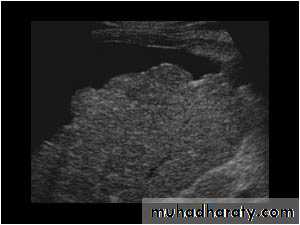

LiverUltrasound : The normal liver parenchyma is of uniform echotexture with portal and hepatic vessels. The normal liver size and shape is variable. Focal masses are noted as alteration of normal echo pattern. They can be divided into cysts, solid or complex masses.

In practice, it is difficult to distinguish benign and malignant lesions unless the mass is clearly a simple cyst.

When multiple masses are seen, metastatic disease is the likely diagnosis. Other differential diagnosis include multiple abscesses and multiple hemangiomas.